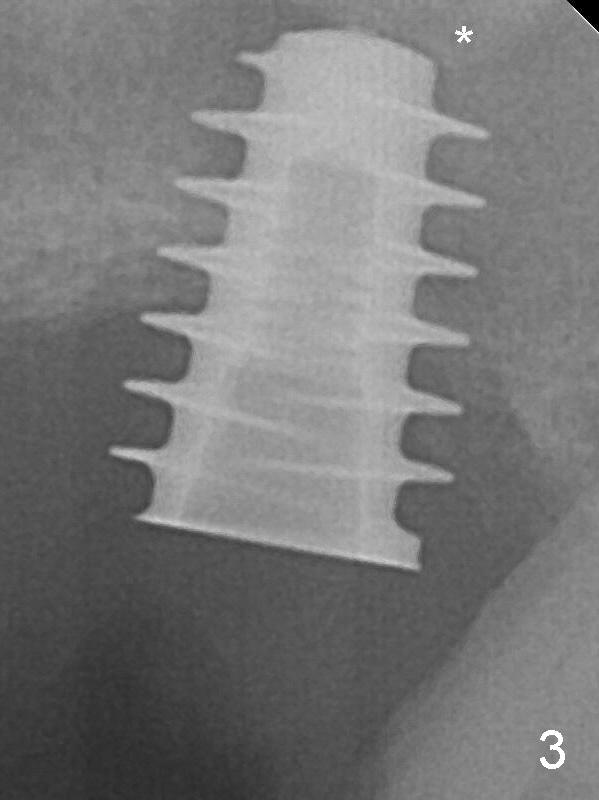

After placement of PRF membrane and bone graft (allograft, autogenous bone and Osteogen, Fig.3 *), a 6x9 mm IBS implant is placed with insertion torque of 30 Ncm.  It appears that the fins of the implant slice into the bone at high magnification for engagement.  Following further placement of the implant, bone graft is packed into the distal portion of the socket (Fig.4 <).  The mesial gingiva is so thick that it is impossible to place bone graft mesial to the implant.

Fins of IBS Implant Last Next